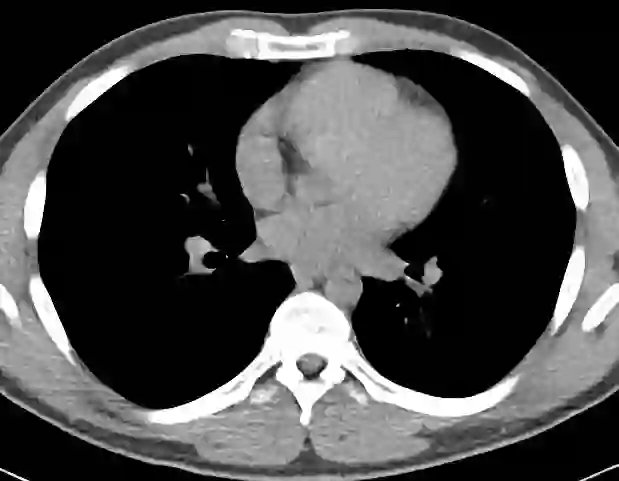

We propose a novel continual self-supervised learning (CSSL) framework for simultaneously learning diverse features from multi-window-obtained chest computed tomography (CT) images and ensuring data privacy. Achieving a robust and highly generalizable model in medical image diagnosis is challenging, mainly because of issues, such as the scarcity of large-scale, accurately annotated datasets and domain shifts inherent to dynamic healthcare environments. Specifically, in chest CT, these domain shifts often arise from differences in window settings, which are optimized for distinct clinical purposes. Previous CSSL frameworks often mitigated domain shift by reusing past data, a typically impractical approach owing to privacy constraints. Our approach addresses these challenges by effectively capturing the relationship between previously learned knowledge and new information across different training stages through continual pretraining on unlabeled images. Specifically, by incorporating a latent replay-based mechanism into CSSL, our method mitigates catastrophic forgetting due to domain shifts during continual pretraining while ensuring data privacy. Additionally, we introduce a feature distillation technique that integrates Wasserstein distance-based knowledge distillation (WKD) and batch-knowledge ensemble (BKE), enhancing the ability of the model to learn meaningful, domain-shift-robust representations. Finally, we validate our approach using chest CT images obtained across two different window settings, demonstrating superior performance compared with other approaches.

翻译:我们提出了一种新颖的持续自监督学习框架,用于同时从多窗位获取的胸部计算机断层扫描图像中学习多样化特征,并确保数据隐私。在医学影像诊断中构建鲁棒且高度可泛化的模型具有挑战性,主要源于大规模精确标注数据集的稀缺性以及动态医疗环境中固有的领域偏移问题。具体而言,在胸部CT中,这些领域偏移常由针对不同临床目的优化的窗位设置差异引起。以往的持续自监督学习框架通常通过复用历史数据来缓解领域偏移,但由于隐私限制,这种方法往往不切实际。我们的方法通过在未标注图像上进行持续预训练,有效捕捉不同训练阶段中已有知识与新信息之间的关联,从而应对这些挑战。具体而言,通过将基于潜在重放的机制融入持续自监督学习,我们的方法在确保数据隐私的同时,缓解了持续预训练中因领域偏移导致的灾难性遗忘。此外,我们引入了一种特征蒸馏技术,该技术整合了基于Wasserstein距离的知识蒸馏与批次知识集成,增强了模型学习具有意义且对领域偏移鲁棒的表征能力。最后,我们使用两种不同窗位设置获取的胸部CT图像验证了所提方法,结果表明其性能优于其他现有方法。